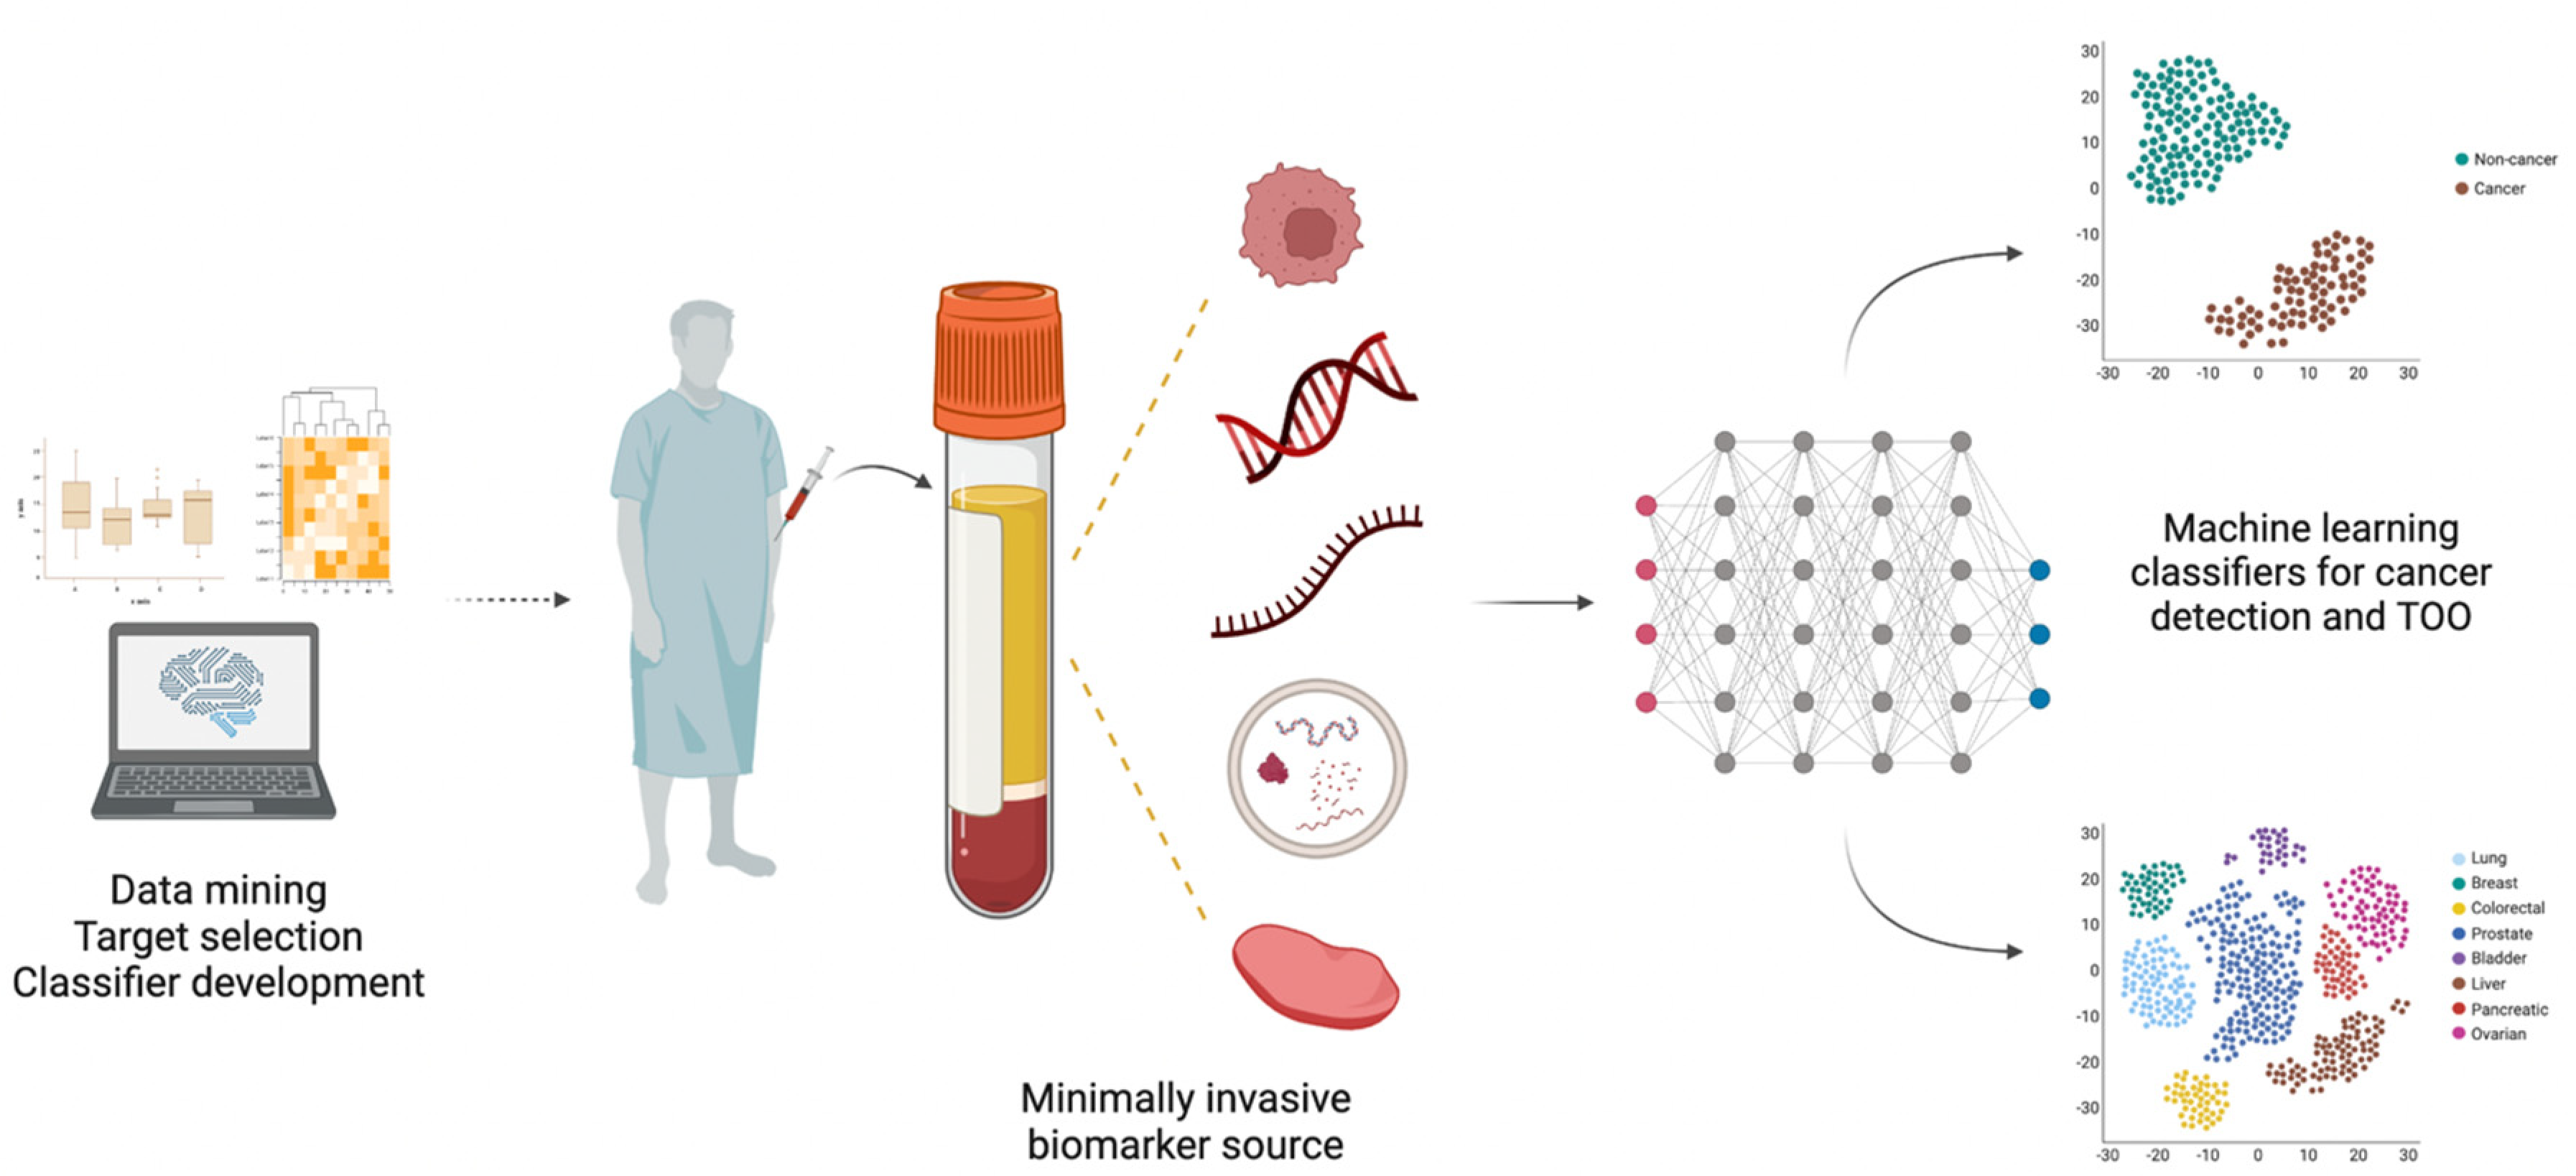

00153-X/asset/006e6fd0-f9ca-4929-a281-d4c073f2d667/main.assets/gr3_lrg.jpg)